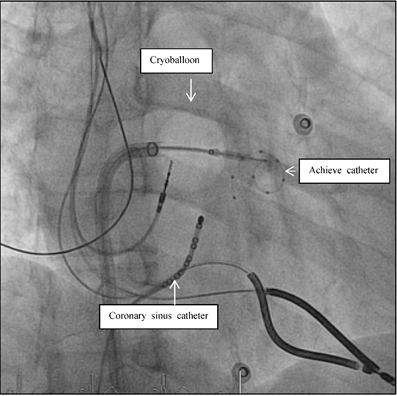

Patient 1 was a 45 years old male and carrier of a dual-chamber ICD. The diagnosis of HCM was made seventeen years ago. He had no catheter-based septum ablation in the past. The long duration of HCM and the systolic anterior movement with moderate mitral regurgitation lead to a dilated LA (Figure 1). Figure 2 shows pressure tracings demonstrating the Brockenbrough-Braunwald-Morrow sign during cardiac catheterization. PAF was first diagnosed ten years before referral. In the past, he had emergent cardioversion on one occasion. He had never been treated with amiodarone; he was on Verapamil and oral anticoagulant therapy. Currently, AF onset resulted in such a hemodynamic impairment that he was subject to intensive care unit. Here an immediate external electrical cardioversion was necessary to stabilize the patient. Even in sinus rhythm the patient suffered from clearly elevated LA pressure as seen in Figure 3.

Figure 1

a,b,c: Transthoracic two dimensional echocardiography (2D, 1a) and transesophageal echocardiography (2D/3D, 1b and 1 c) in patient 1 with advanced disease, moderate mitral regurgitation and dilated left atrium. SAM systolic anterior movement.